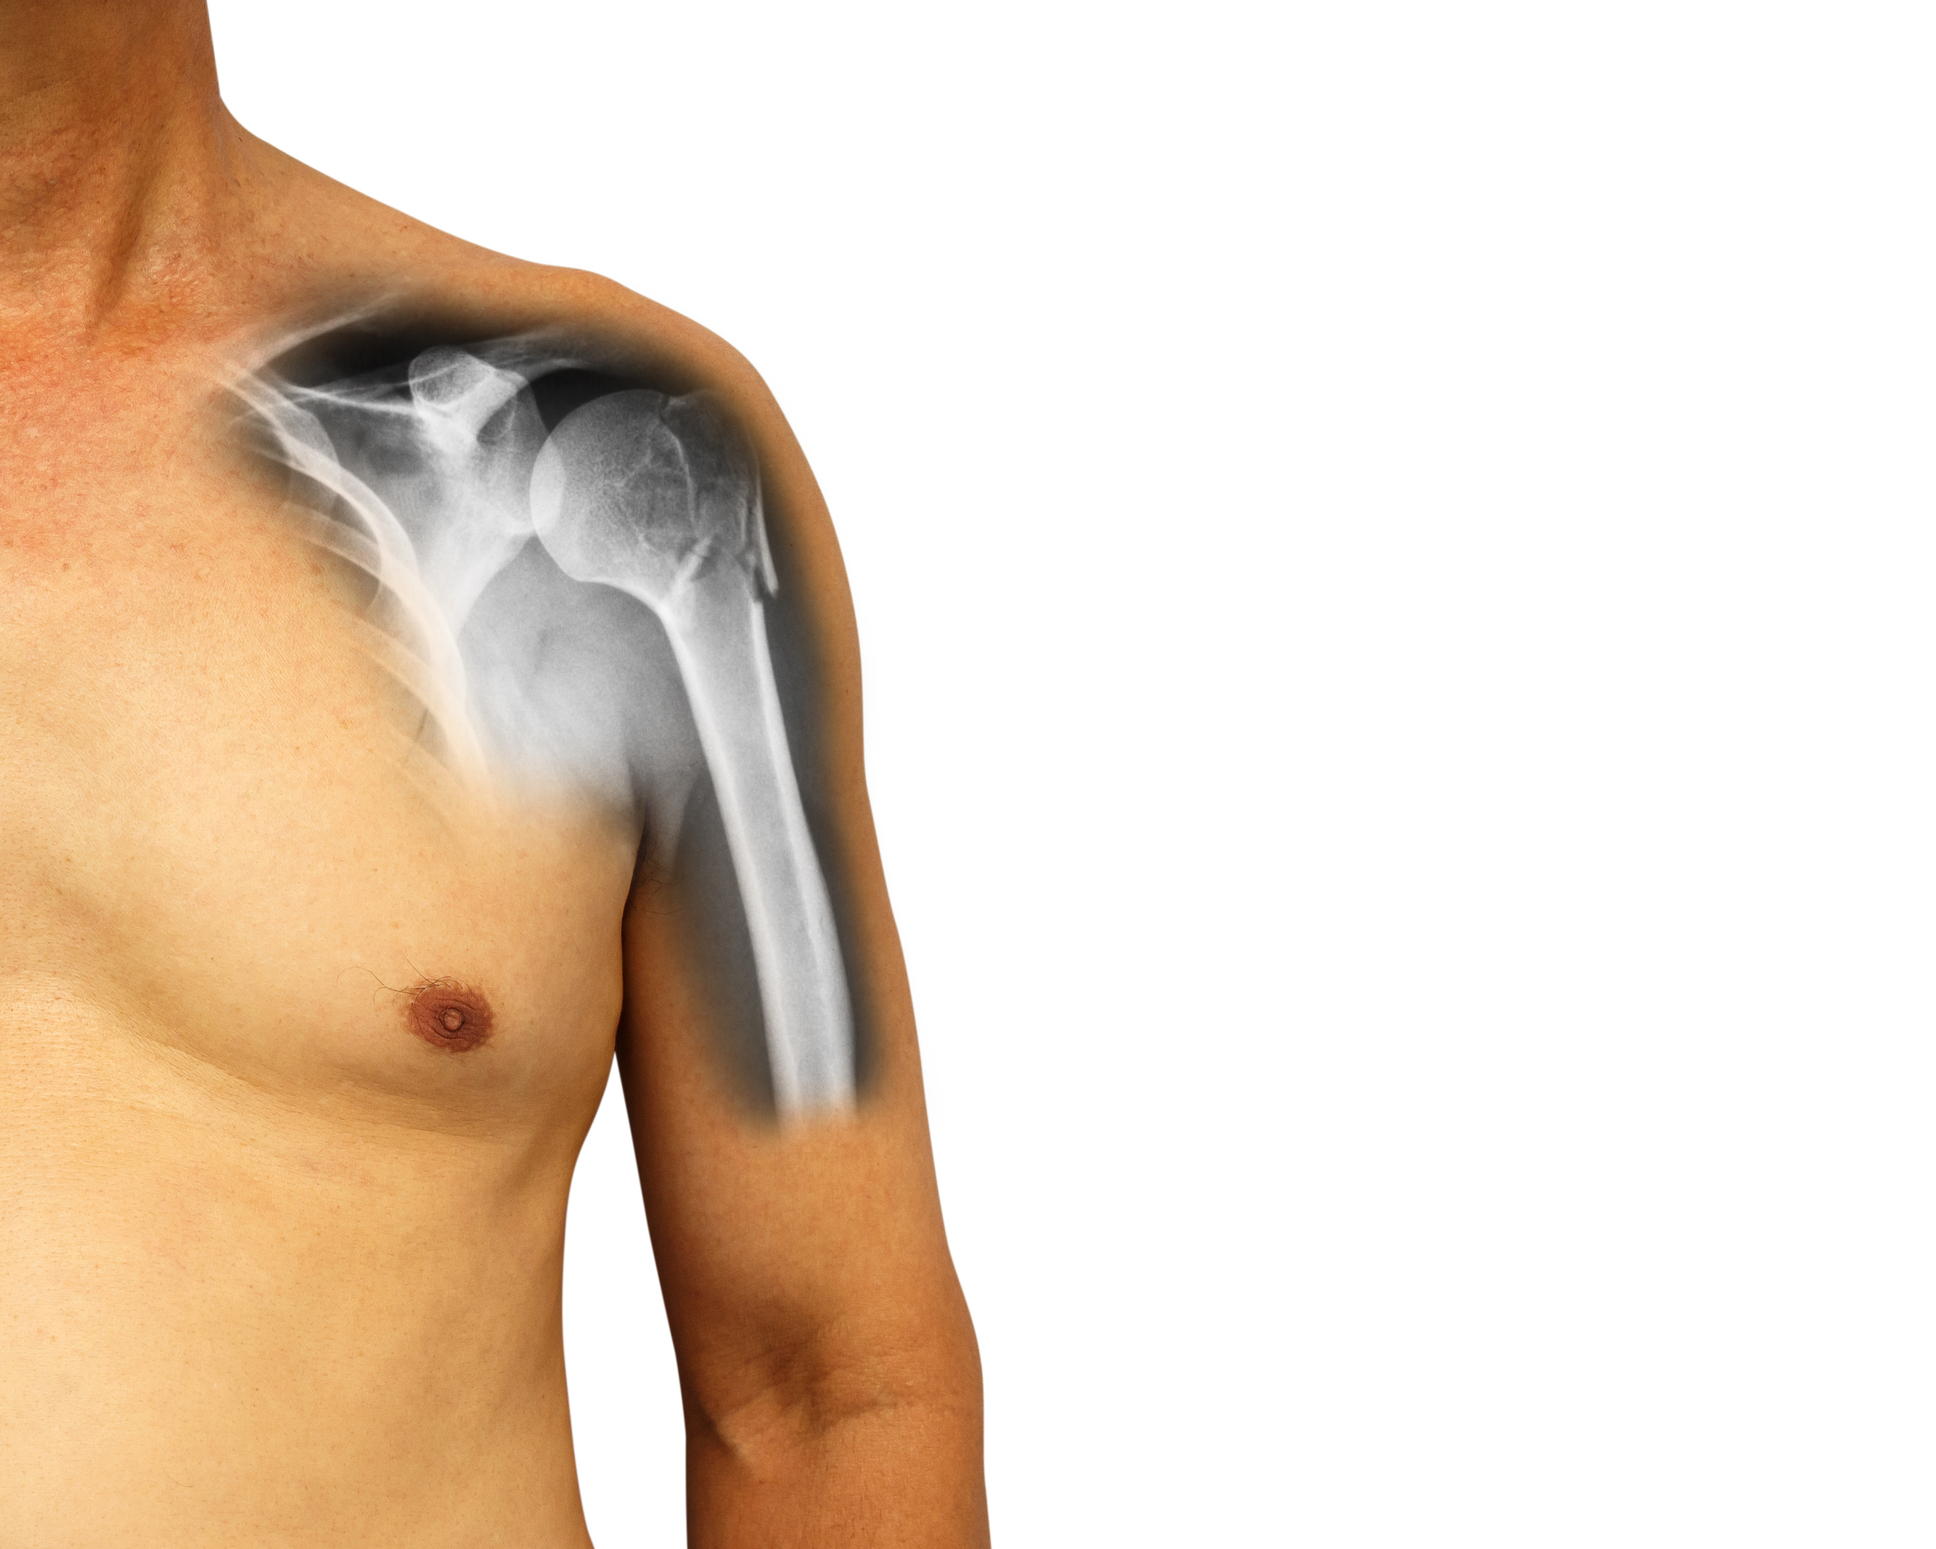

Zlome nadlahtnice delimo v grobem na 3 skupine – zlom zgornjega, srednjega ali spodnjega dela. Kakšno zdravljenje bo primerno je v veliki meri odvisno od lokacije zloma.

Zlomi zgornjega dela nadlahtnice (proksimalni zlom)

Večino zlomov proksimalnega dela nadlahtnice je mogoče zdraviti brez operacije, če kostni fragmenti niso pretirano premaknjeni. Če so prisotni veliki premiki se pogosto opravi operacija, da se omogoči optimalno okolje za celjenje kosti.

Kaj pa če je potrebna operacija? Operacija običajno vključuje fiksacijo fragmentov zloma s ploščami in vijaki. Mobilizacija s specialno fizioterapijo se lahko začne takoj po operaciji – zlomom zgornjega dela je namreč pogosto pridružena poškodba ramena.